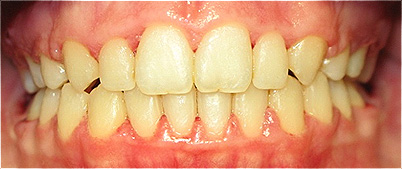

Apinhamento dentário com os dentes caninos em desoclusão (classe II, divisão 2).

![]() |

Após dois anos de tratamento ortodôntico.